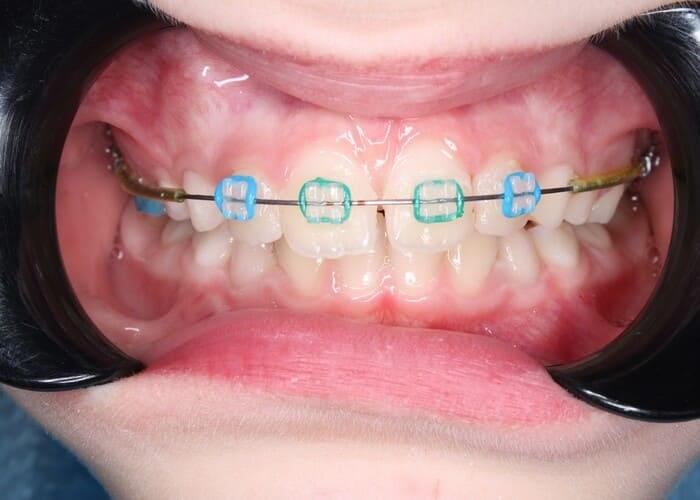

Незначні, на перший погляд, нюанси в естетичному вигляді зубощелепної системи можуть створювати як естетичний дискомфорт для пацієнта, так і функціональні порушення. Тому дуже важливо, аби діти, підлітки спостерігались у лікаря-ортодонта і були на контролі принаймні раз на шість місяців для того, аби ідентифікувати проблему або фактори ризику розвитку певних проблем і можна було вчасно їх усунути. Знімна, незнімна апаратура та робота з брекет-системою, з брекет-системами різних видів — це те, чим у Центрі Дитячої Стоматології проводиться корекція прикусу. Ми робимо це ефективно та прогнозовано, як у даному клінічному випадку.

Ортодонтичне лікування брекет системою. Алєксєєва Аліна.

Лікування брекет-системою у підлітків займає особливе місце, тому що потребує, з одного боку, розуміння біомеханіки і впливу на зубощелепну систему дорослої людини, і разом з тим, потребує уважності, якою має володіти дитячий стоматолог. Тому таке лікування часто є складною процедурою як біомеханічно, так і з точки зору комунікації з юними пацієнтами та їхніми батьками. Але в Центрі Дитячої Стоматології ми знаємо, як це робити, і тому досягаємо гарних результатів, як у даному клінічному випадку.